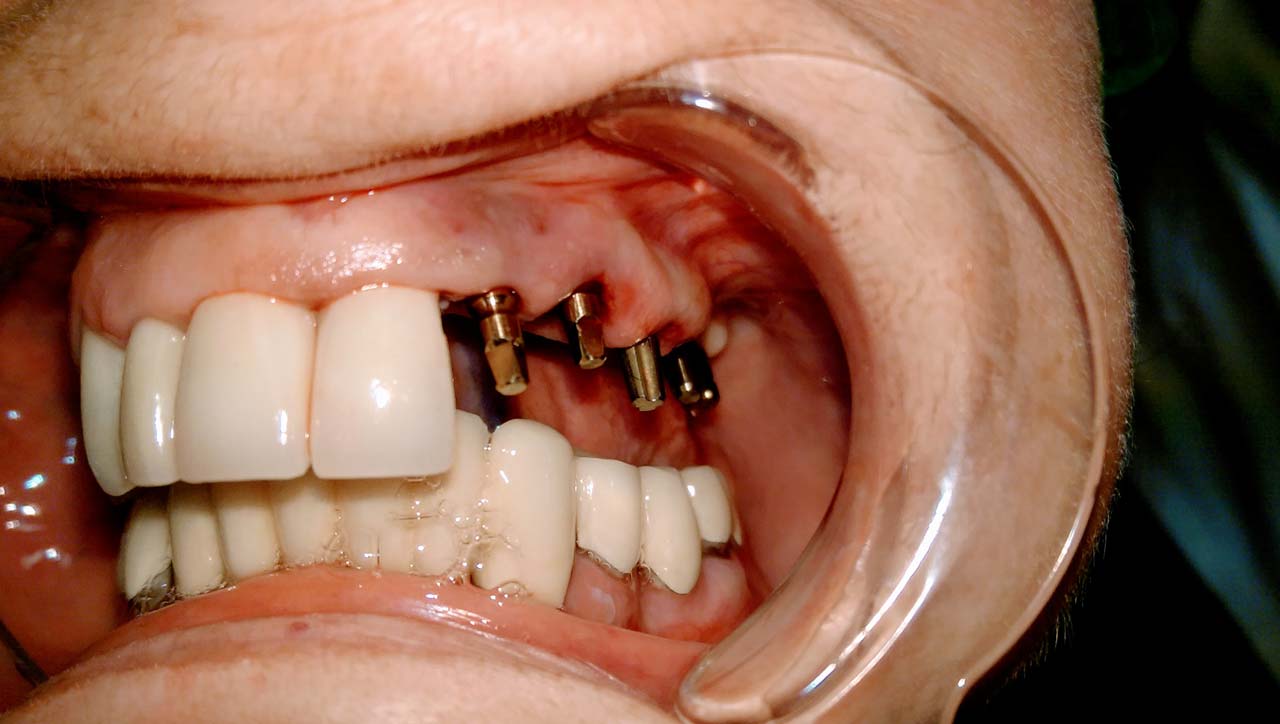

Teljes fogatlanság helyreállítása 2 nap alatt

Teljes fogatlanság helyreállítása 2 nap alatt azonnal terhelhető svájci IHDE implantátumokkal és PMMA műanyag hidakkal. Intraorális szkennerrel vettünk lenyomatot az implantáció után, és erre a digitális mintára készítette el a fogtechnika a hidak digitális tervezését, majd faragta ki műanyagból. Ezt a gyors munkát az azonnal terhelhető implantátumok és a digitális lenyomat, tervezés segítségével tudtuk megcsinálni mindössze 2 nap alatt. Dr. Kelemen Péter és a Symbion Fogtechnika munkája.